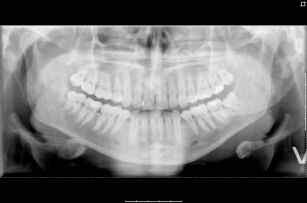

Røntgen av kjeve

Røntgen av kjeve (OPG) gir oss ei framstilling over alle tennene, tannrøter og kjeve (panoramabilde). OPG blir ofte tatt før ein fjerner visdomstenner, rutine før hjarteoperasjon, tannstatus før ein eventuell strålebehandling og ved spørsmål om brot.